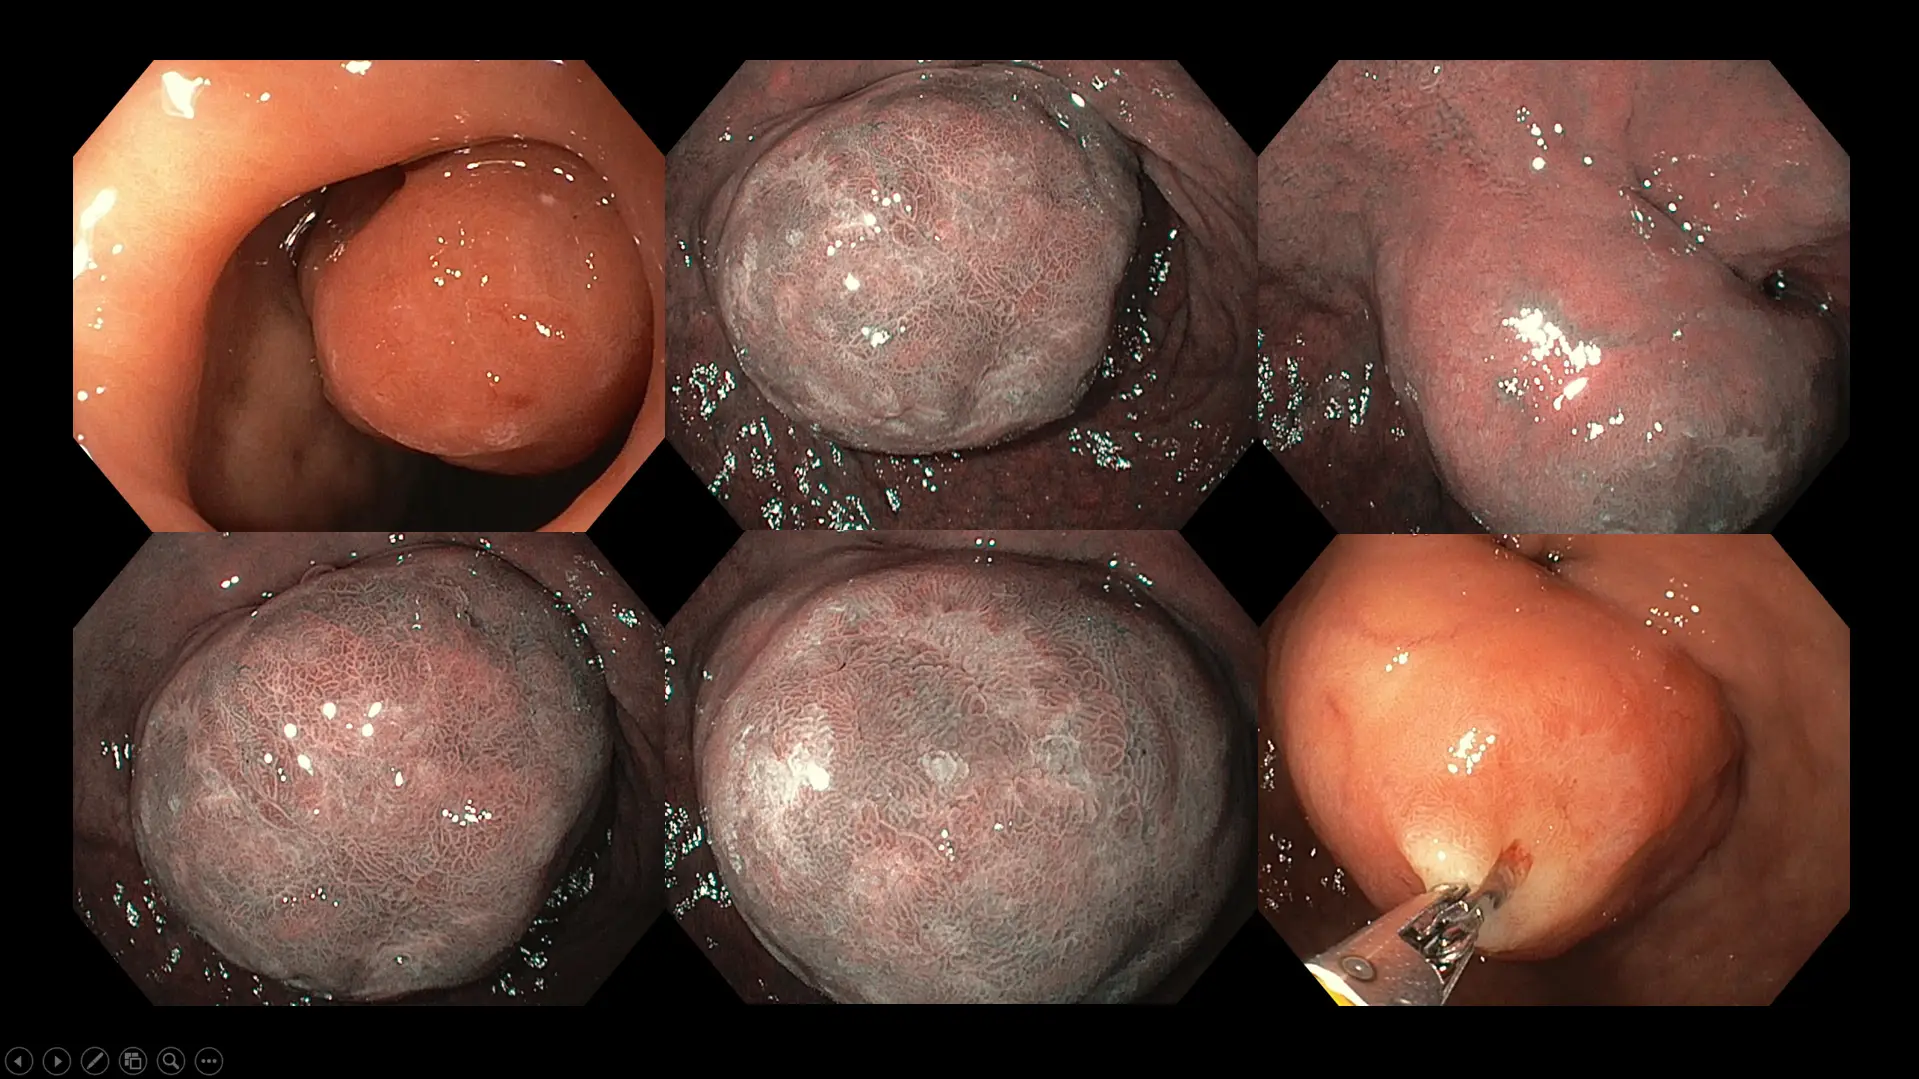

Figure 8: Case of a large duodenal (first part of the small bowel) tumor in a patient with long-standing abdominal fullness, bloating, and mild crampy discomfort. Although surgical removal was offered due to the size of the polyp, our patient chose a conservative watch-and-wait approach because of her advanced age and multiple medical conditions.